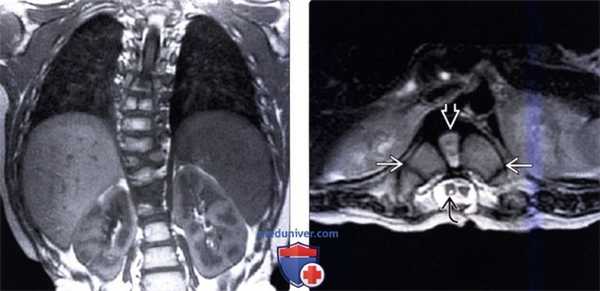

(Слева) На фронтальном Т1-ВИ (миеломенингоцеле, сколиоз) определяется правосторонняя сколиотическая деформация грудного отдела позвоночника с множественными аномалиями формирования позвонков в средне- и нижнегрудном отделе. У этого пациента также обнаружена диастематомиелия (не показана).

(Справа) На аксиальном Т2-ВИ (миеломенингоцеле, диастематомиелия) на уровне Т10 виден причудливой формы аномально расширенный позвонок, представляющий собой «позвонок-бабочку» с патологически измененным межпозвонковым диском. Обратите также внимание на сирингомиелию правой половинки спинного мозга.

(Слева) Т2-ВИ, сагиттальная проекция: тяжелая остроугольная кифотическая деформация верхне-грудного отдела позвоночника.

На вершине деформации определяется в значительной степени гипопластичный передний полу-позвонок, а также нетипичен вид остальных позвонков, свидетельствующий о множественных аномалиях формирования и сегментации позвонков.

(Справа) Т1-ВИ, аксиальная проекция (тяжелый кифосколиоз): нормальный спинной мозг на фоне сужения окружающего участка спинномозгового канала связанного с множественными врожденными аномалиями формирования позвонков.